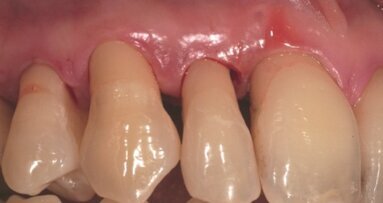

44-letnia pacjentka zgłosiła się do prywatnej kliniki PGG w celu leczenia przyzębia w okolicy prawych zębów trzonowych szczęki (Ryc. 1). Z wywiadu medycznego wynikało, że pacjentka jest ogólnie zdrowa. Była wcześniej leczona z powodu przewlekłego zapalenia przyzębia z wykorzystaniem metod niechirurgicznych. Wykonano diagnostyczne zdjęcie radiologiczne (Ryc. 2). Stwierdzono ubytek przyzębia brzeżnego i ubytek pionowy o zwiększonej przezierności dla promieniowania. W badaniu klinicznym stwierdzono izolowane głębokie kieszonki (Ryc. 3). Klinicznie nie zanotowano zwiększonej ruchomości zębów.

Gojenie przebiegało bez powikłań, po 6 miesiącach uzyskano całkowite wygojenie. W okresie gojenia wykonywano zębowe zdjęcia radiologiczne w celu oceny zmian mineralizacji materiału kościozastępczego w czasie. Widoczne było jednoznacznie powstawanie kości w obrębie ubytku kostnego. Na zdjęciach radiologicznych widoczna była zwiększona mineralizacja kości wokół zębów. Pacjentkę badano co roku. Po 6 latach od zakończenia leczenia (Ryc. 7) wykonano kolejne zdjęcie radiologiczne (Ryc. 8), które wykazało całkowite wygojenie ubytku kostnego wokół zębów.